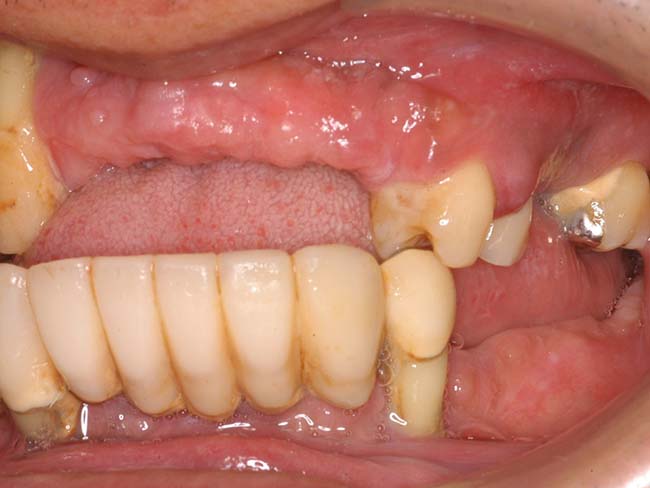

若い歯周病患者(30代)のAll-on-4

| 患者さま情報 | 治療期間 | 治療費 |

|---|---|---|

| 30代 男性 | 1年4ヶ月 | 2,491,000円 |

リスクや副作用

・保険外で高い

・治療が適応とならないケースがある。

・十分なメンテナンスがないと、失敗やトラブルを招く可能性がある。

治療経験・技術がある医師による治療が必要となる。

・外科的治療が必要